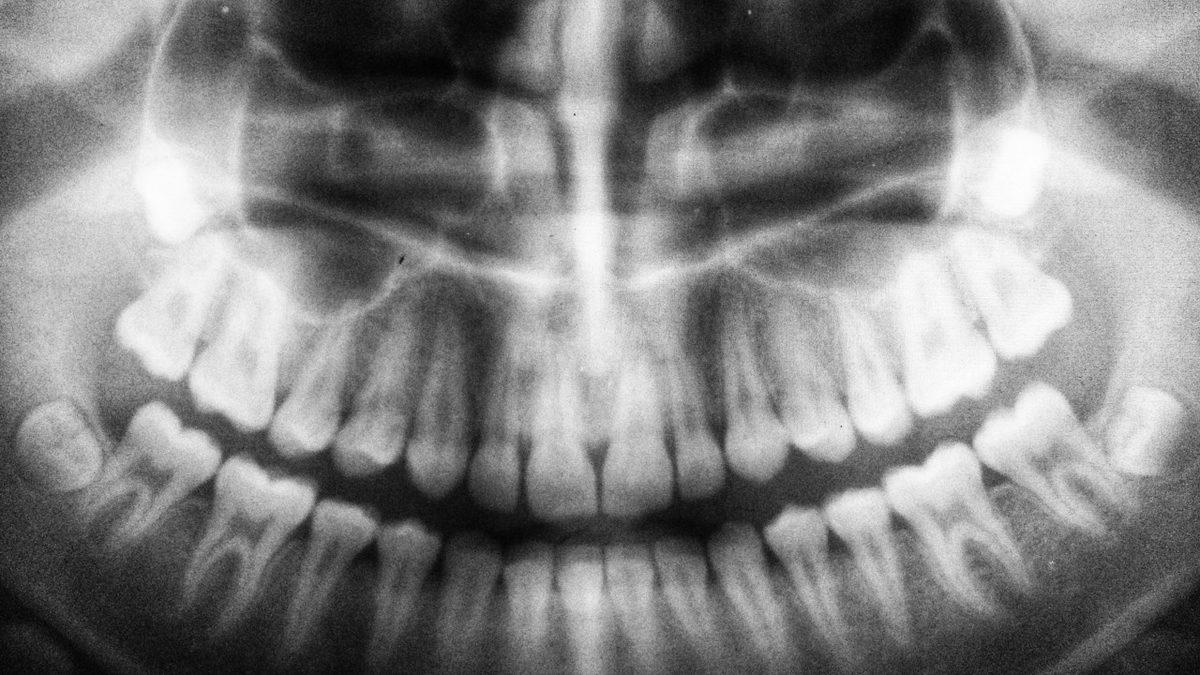

Kemiklerinin hepsi yerli yerinde olan Turkana’ya ait tespit edilebilen tek şey, çene kemiğindeki tuhaflıklardı. Süt dişlerinden biri eksikti ve bu da "Gingivitis" adı verilen bir diş eti rahatsızlığının bariz göstergesiydi. Araştırmalara göre Kenya’da yaşadığı bilinen bu kişi, hastalığı sebebiyle enfeksiyon kapıp muhtemelen kan zehirlenmesinden ölmüştü.

Kabwe de yaklaşık 400 bin yıl önce yaşamış ve şiddetli diş çürüklerine ek olarak, diş eti rahatsızlığıyla mücadele etmişti. Bu kişinin kafatası, dişlerin gömülü olduğu çene kemiğini etkileyen çok sayıda diş boşluğuna ve apseye sahipti.

Turkana çocuğu gibi Kabwe’yi de sıra dışı yapan şey ise, antik insanlarda nadiren ağız ve diş problemleri görülmesiydi. Çünkü tarımın başlangıcına dek, yaklaşık 10 bin yıl öncesine kadar ilk insanların besinleri oldukça sınırlıydı ve şekerli beslenme olasılıkları oldukça düşüktü.